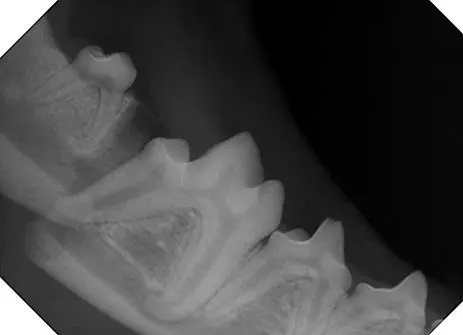

Figure 1. Radiograph of a dog’s mandible after it has been fractured during an altercation with another dog

Broken jaws resulting from periodontal disease are often seen near the mandibular 1st molar tooth due to severe bone loss around the tooth. The bone loss weakens the mandible, predisposing it to fracture when the patient does something as simple as jumping off a piece of furniture or biting down on a piece of hard kibble.

At Animal Dental Care and Oral Surgery, most mandibular fractures treated have occurred because of a trauma or as a result of periodontal disease. Common traumatic events include vehicular trauma or an altercation with another dog.